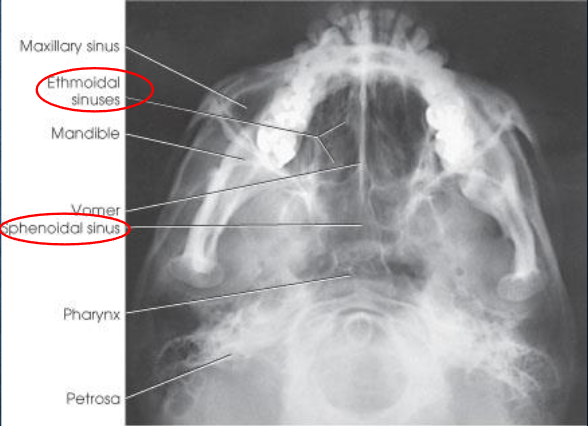

SMV (Schuller) skull

SMV (Schuller) skull image criteria

no rotation or tilt:

equal distance from lateral border of skull to mandibular condyles

symmetric petrous pyramids

penetration sufficient to demonstrate structures of cranial base

superimposition of mental protuberance over anterior frontal bone, indicating full neck extension

mandibular condyles anterior to petrous pyramids